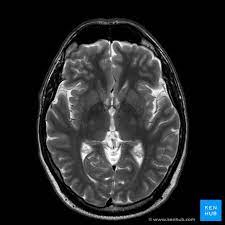

A brain MRI offers a non-invasive way to get a detailed view of the brain. It uses magnetic fields and radio waves to create detailed images, helping doctors identify any abnormalities. For Riya, it was the key to unlocking the mystery behind her symptoms.

The MRI results revealed a benign brain tumor, something that could be managed with proper medical intervention. While the news was initially overwhelming, Riya felt a sense of relief. Finally, she had an answer, and a clear path to recovery lay ahead.